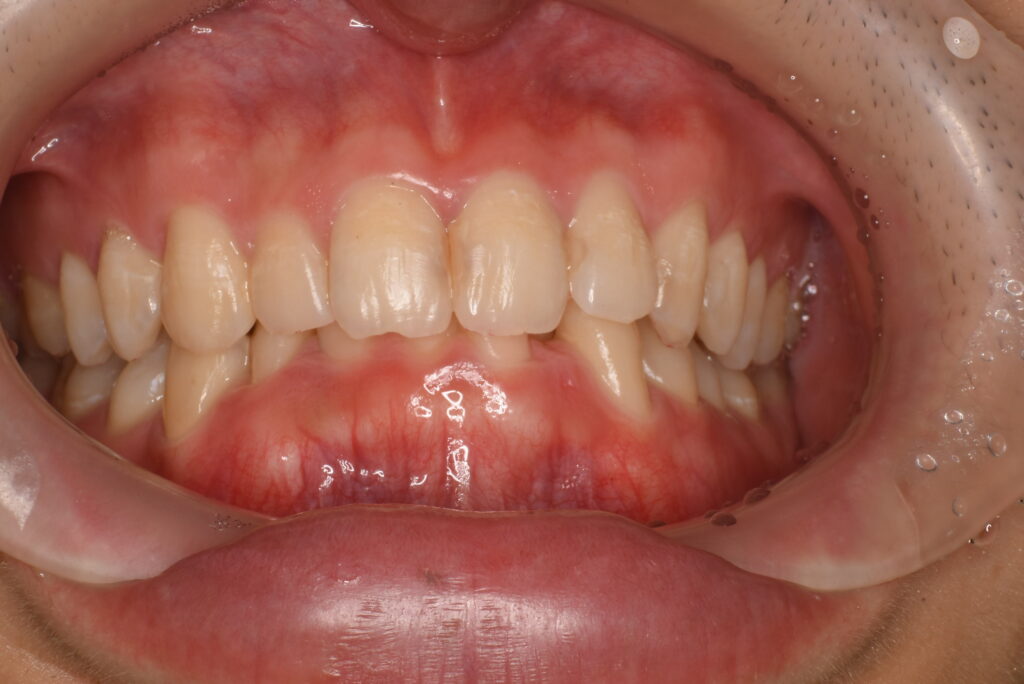

- BEFORE

- AFTER